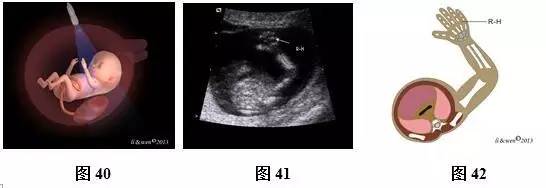

(四)11~13+6孕周胎儿肢体扫查方法及观察内容

超声扫查方法:声束平面通过一侧上肢作冠状或矢状扫查(图40),即可获得一侧上肢冠状或矢状切面(图41,42);声束平面通过一侧下肢作冠状或矢状扫查(图43),即可获得一侧下肢冠状或矢状切面(图44,45)。对每一肢体按此方法逐一扫查,不漏检任何一条肢体。

标准切面判断标准:上肢冠状或矢状切面:应显示上臂及其内的肱骨,前臂及其内尺、桡骨,手掌及手指。下肢冠状或矢状切面:应显示大腿及其内的股骨,小腿及其内胫、腓骨,足。

主要观察内容:骨的长度、回声强度、数目及形态,肢体是否存在或缺如,手及足形态是否正常。此孕期胎儿呈张手状态,易观察到手指数目。

注:R-H为右手;R-F为右足

图40~45 11~13+6孕周胎儿肢体扫查方法及声像图及模式图。图40上肢扫查方法模式图;图41、42右上肢冠状切面声像图及模式图;图43下肢扫查方法模式图;图44、45下肢矢状切声像图及模式图